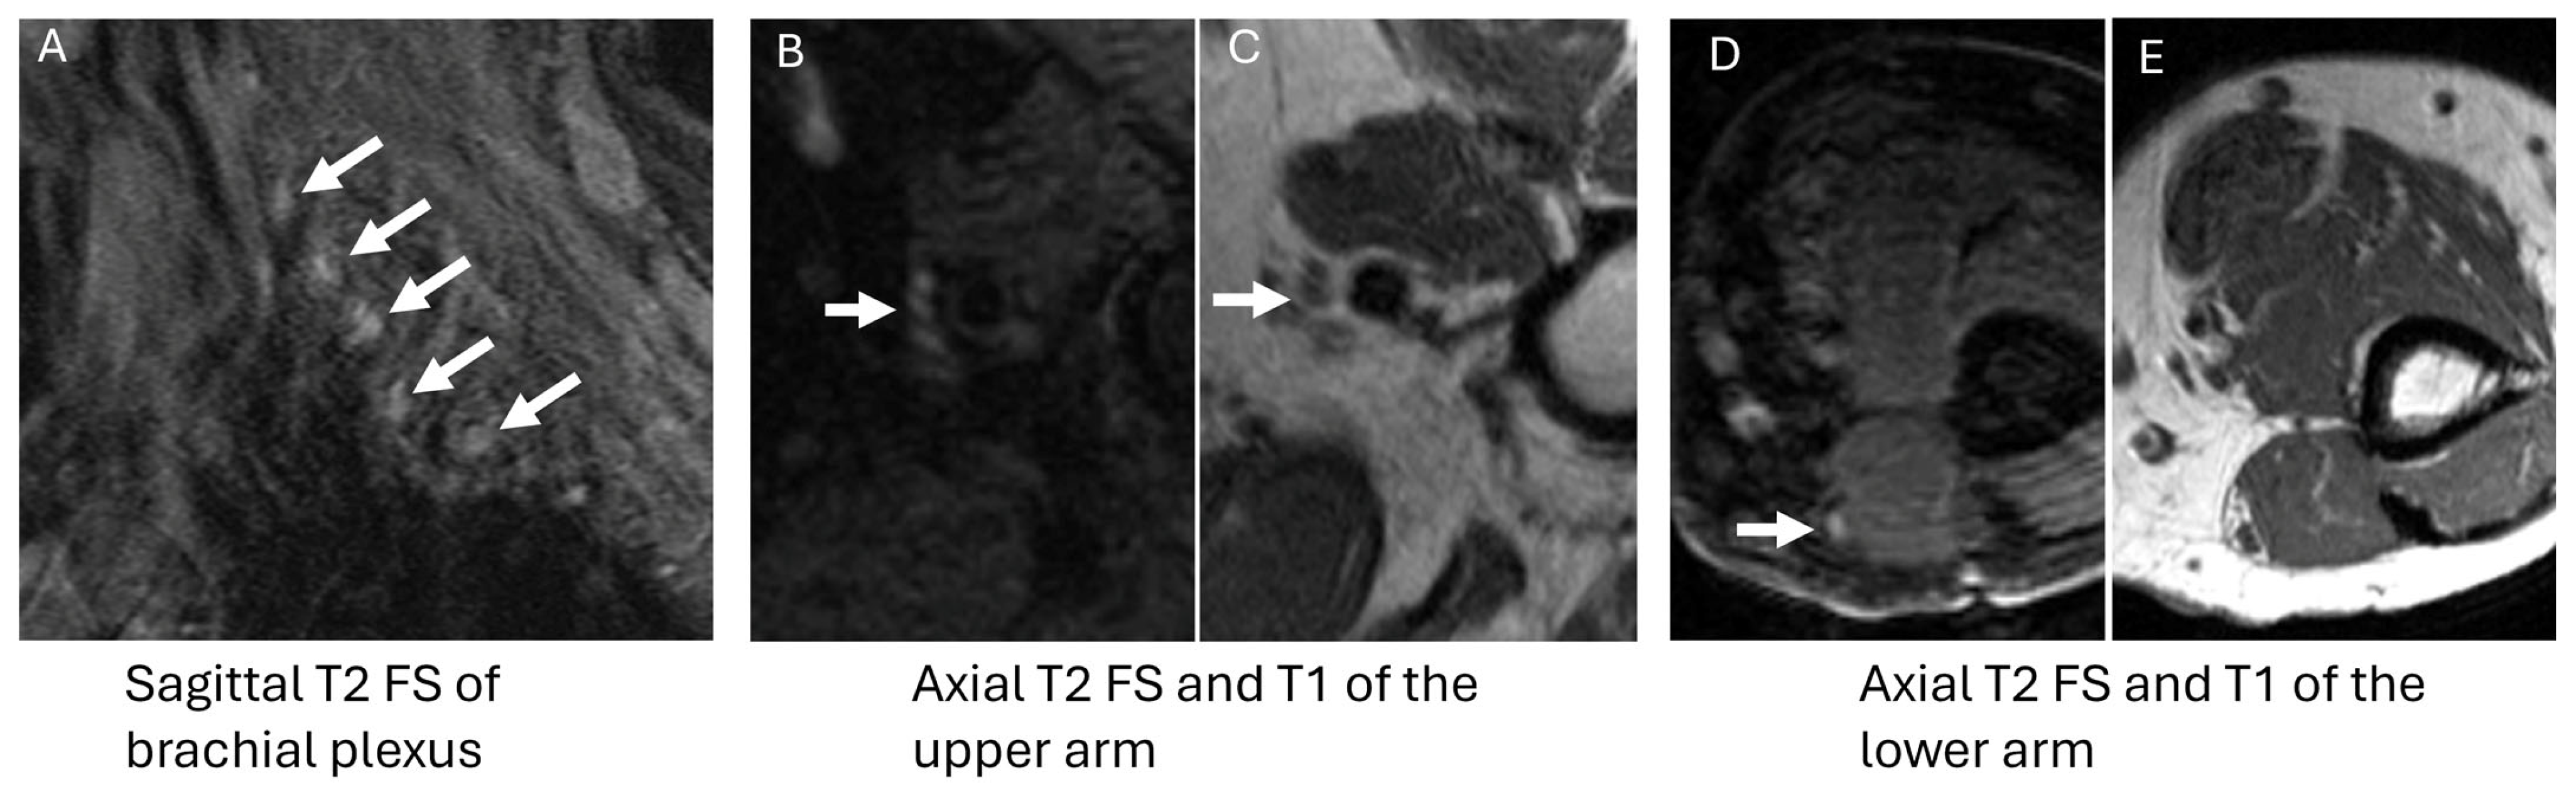

3.1. POEMS Syndrome

| DADS-M |

|

| CANOMAD |